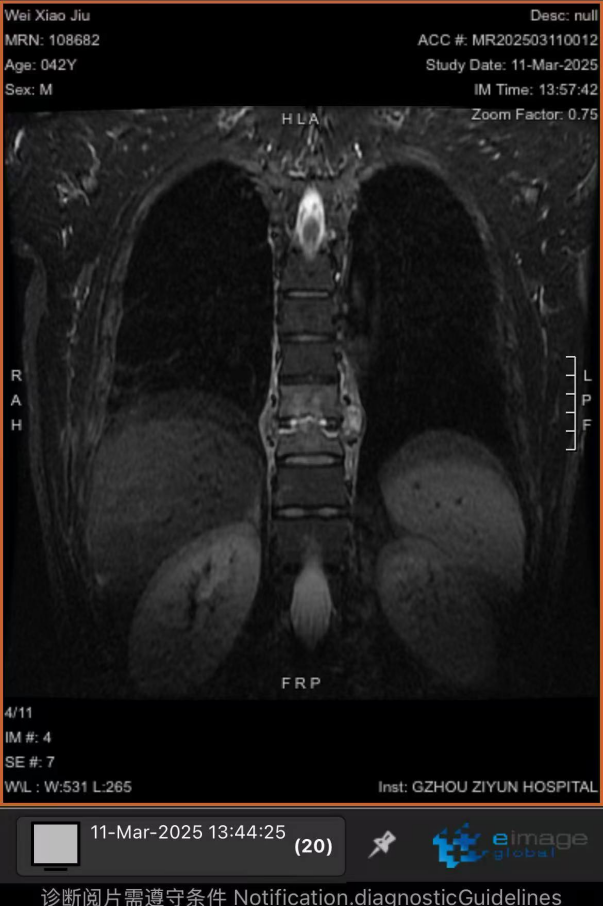

以為是干活勞累,卻突發(fā)癱瘓 “我以為是最近做活路太累了,導(dǎo)致的腰酸背痛,哪曉得突然就癱了!真的感謝周醫(yī)生他們的幫助,把我救回來(lái)了!”談起這番經(jīng)歷,張先生仍心有余悸。 據(jù)悉,今年三月初,42歲的張先生(化名)因胸背疼痛一個(gè)月未進(jìn)行相關(guān)治療,伴隨疼痛進(jìn)行性加重后,入院前3天出現(xiàn)雙下肢無(wú)力、不能行走、大小便失禁等情況。入院時(shí),體查其雙下肢肌力為0,自肋弓以下喪失知覺(jué),無(wú)法坐立,且影像學(xué)檢查顯示,其胸椎上段被結(jié)核性膿腫及壞死骨嚴(yán)重壓迫,脊髓持續(xù)受損。 "每耽誤一分鐘,神經(jīng)壞死風(fēng)險(xiǎn)就增加一分?;颊吣茉僬酒饋?lái)的可能也就減少一分,對(duì)患者家庭是災(zāi)難性后果,我們必須為他爭(zhēng)取時(shí)間。"貴陽(yáng)市公共衛(wèi)生救治中心外三科副主任周波告訴記者;通常情況下,脊柱結(jié)核手術(shù)需2-3周抗結(jié)核治療后再行手術(shù)。但面對(duì)張先生不斷惡化的脊髓損傷,他們必須與患者一同與時(shí)間賽跑:打破常規(guī)的急診手術(shù)決策,進(jìn)過(guò)迅速且嚴(yán)謹(jǐn)?shù)臅?huì)診決策后,靜脈給予一次抗癆治療,團(tuán)隊(duì)當(dāng)機(jī)立斷采用"脊柱前后路聯(lián)合"急診手術(shù)為張先生進(jìn)行施救。“我們首先從前路開胸,清除椎體前方膿腫及壞死組織,植入鈦網(wǎng)替代部分椎體功能,由于椎體跳躍性骨質(zhì)破壞,前路固定不牢固,立即行后路手術(shù),通過(guò)椎弓根釘棒系統(tǒng)實(shí)現(xiàn)脊柱三維穩(wěn)定,再次行后路減壓,雙路徑手術(shù)一次性徹底清除病灶,減壓更充分,復(fù)發(fā)幾率更小。 患者術(shù)前X片 患者胸部CT 患者胸椎核磁共振 術(shù)后復(fù)查的X線 該患者在術(shù)后第一天身體感知覺(jué)有較明顯恢復(fù),第5天開始腳趾恢復(fù)活動(dòng),兩周時(shí)肌力恢復(fù)至3級(jí)以上,截至昨日記者在現(xiàn)場(chǎng)目睹,雙腿已經(jīng)可以自主抬放。周波副主任表示,急性脊髓損傷的黃金救治窗口極短,聯(lián)合入路既能快速減壓又確保長(zhǎng)期穩(wěn)定性,這是恢復(fù)超預(yù)期的關(guān)鍵。預(yù)計(jì)一個(gè)月左右,這位患者就能重新自主行走了。 本次手術(shù)團(tuán)隊(duì)的幾位醫(yī)生正在叮囑患者出院后的注意事項(xiàng) 左起:羅善鵬,石頭,周波,左樂(lè) 專家提示: 腰痛≠腰椎勞損 這些信號(hào)要警惕 針對(duì)近年多發(fā)的"腰痛誤診"現(xiàn)象,周主任特別提醒:腰椎結(jié)核多以持續(xù)性腰痛為主,多伴低熱、盜汗、體重下降等結(jié)核中毒癥狀;而腰椎間盤突出典型表現(xiàn)為腿痛腿麻等。一定要注意的是當(dāng)出現(xiàn)腰痛合并下肢無(wú)力、大小便功能障礙時(shí),無(wú)論屬于哪一種情況都需立即就醫(yī)。 據(jù)統(tǒng)計(jì),我國(guó)結(jié)核感染人群超2億,其中5%-10%的肺外結(jié)核可累及脊柱。專家強(qiáng)調(diào),骨結(jié)核雖發(fā)病率低,但致殘率高,早期規(guī)范治療可避免災(zāi)難性后果。 專家簡(jiǎn)介 周波,男,43歲,副主任醫(yī)師,中國(guó)抗癆協(xié)會(huì)結(jié)核病健康促進(jìn)分會(huì)委員,中華醫(yī)學(xué)會(huì)貴陽(yáng)市骨科分會(huì)委員、貴陽(yáng)市康復(fù)醫(yī)學(xué)會(huì)委員,貴陽(yáng)市骨科質(zhì)量委員會(huì)委員,貴陽(yáng)市艾滋病性病防治協(xié)會(huì)委員,中國(guó)中醫(yī)藥信息學(xué)會(huì)骨科分會(huì)委員,從事臨床醫(yī)學(xué)骨外科專業(yè)15余年,擅長(zhǎng)脊柱結(jié)核及其截癱患者的治療,搶救脊髓功能,擅長(zhǎng)骨與關(guān)節(jié)結(jié)核的診治,髖、膝關(guān)節(jié)置換的治療,術(shù)后療效顯著,有效減少患者的致殘率。在國(guó)內(nèi)學(xué)術(shù)核心雜志發(fā)表學(xué)術(shù)專業(yè)文章15篇。